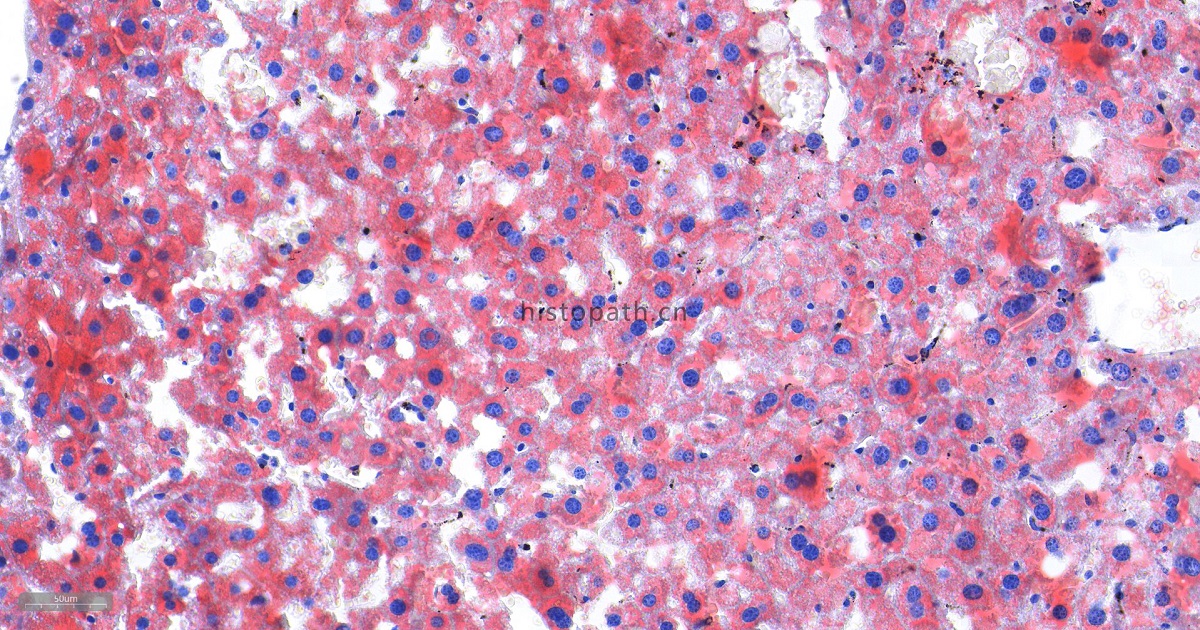

染色结果分析:中性脂肪呈橙红色,细胞核呈蓝色。